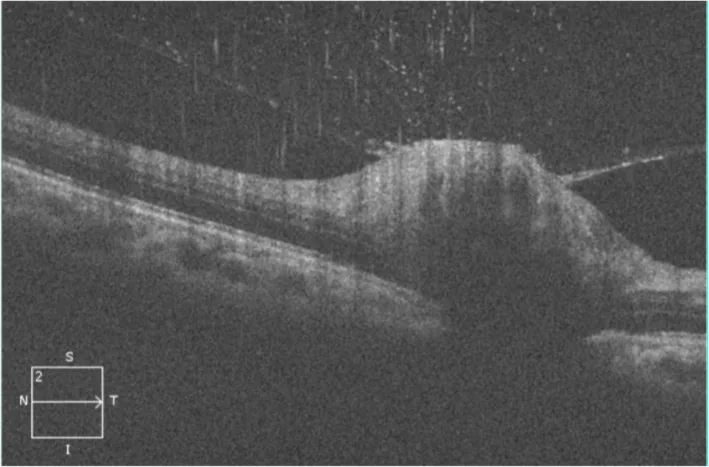

CSDに伴う神経網膜炎では、視神経乳頭から黄斑に及ぶ浮腫が生じ、星芒状白斑(star figure)が特徴的に出現する。B. henselaeの血行播種が視神経や網膜への直接的な菌の侵入を引き起こすと考えられている。